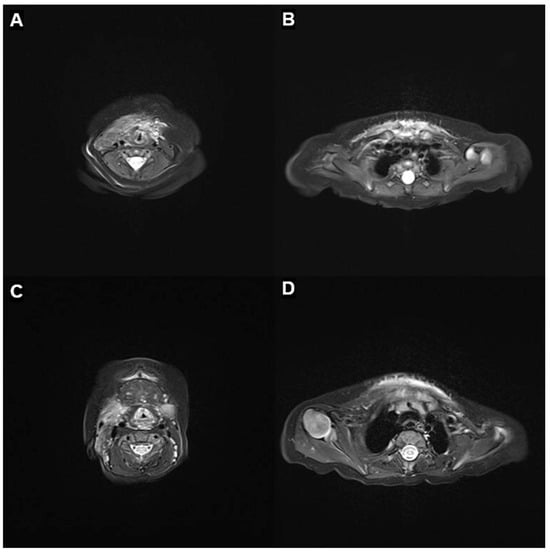

Neonatal Kaposiform Hemangioendothelioma with Kasabach–Merritt Phenomenon Presenting as Severe Airway Obstruction at Birth: A Case Report

Background/Objectives: Kaposiform hemangioendothelioma (KHE) is a rare, locally aggressive vascular tumor of infancy, often complicated by Kasabach–Merritt phenomenon (KMP), a consumptive coagulopathy characterized by severe thrombocytopenia and hypofibrinogenemia. Airway involvement at birth is exceptionally rare and can be life-threatening. This study reports [...] Read more.

Background/Objectives: Kaposiform hemangioendothelioma (KHE) is a rare, locally aggressive vascular tumor of infancy, often complicated by Kasabach–Merritt phenomenon (KMP), a consumptive coagulopathy characterized by severe thrombocytopenia and hypofibrinogenemia. Airway involvement at birth is exceptionally rare and can be life-threatening. This study reports the clinical presentation and treatment course of a full-term male neonate with severe airway obstruction caused by KHE with KMP. Case Presentation: The patient had unremarkable prenatal imaging but presented at birth with severe respiratory distress requiring emergent intubation. Physical examination revealed firm violaceous swelling over the right cervicothoracic region. Laboratory tests showed profound thrombocytopenia (22,000/μL), hypofibrinogenemia (75 mg/dL), and coagulopathy. Imaging findings were consistent with KHE complicated by KMP. Due to bleeding risk, the biopsy was not performed. Initial treatment included platelet and plasma transfusions, intravenous immunoglobulin (IVIG), corticosteroids, and antithrombin III replacement. Vincristine was discontinued owing to gastrointestinal toxicity. Sirolimus therapy was initiated on day 14. Following sirolimus initiation, rapid platelet recovery was observed. At three months, marked tumor regression was documented. After mild recurrence, sirolimus was reintroduced, and the patient remained stable at 16-month follow-up. Conclusions: This case underscores the critical importance of prompt airway stabilization, early recognition of consumptive coagulopathy, and sirolimus-based therapy in managing neonatal KHE with airway involvement. Full article

Show Figures

Figure 1